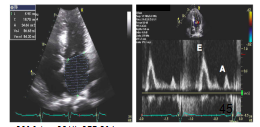

8、二尖瓣口舒张期血流频谱指标1

●Valsalva 动作E/A比值 (1.3—0.6):E/A比值减少≥50%对提示LV充盈压增高具有高度特异性,但是变化幅度较小并不提示舒张功能正常。

●当二尖瓣口血流及二尖瓣环速度测量仍不能确定病人的舒张功能时,Valsava动作还是可以作为一种保留的检查手段。

9、二尖瓣口舒张期血流频谱指标2

10、二尖瓣环运动速度指标

左室舒张功能受损

①室间隔侧e’< 7 cm/s;

②侧壁侧e’< 10 cm/s;

③平均E/e’> 14